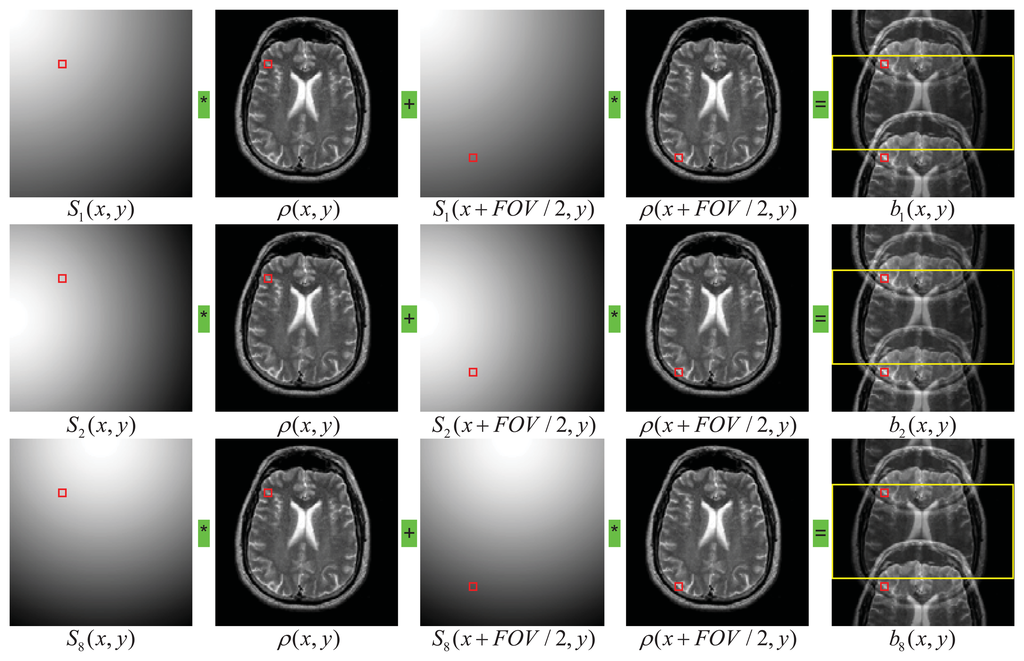

For the model of simple 2D SENSE with an acceleration factor r, the k-space data were regularly undersampled by skipping every r—1 phase encoding lines in the full k-space [13]. Without losing generality, we consider as an example the case of acceleration factor of r = 2 and the number of coils c = 8. For a pixel at location (x, y) in the aliased image, the signals measured by each of the eight coils are given by following equations:

This is a simplified version of the direct problem previously given in Equation (1), which states that the signals at the locations of the two pixels (x, y) and (x+FOV/2, y) are aliased to generate the measured signals in the component coils. The illustration of SENSE is shown pictorially in Figure 1.

In matrix notation, equations in Equation (2) can be expressed in Equation (3), where S is an 8 × 2 matrix whose elements are sensitivities of the coil components at two locations of (x, y) and (x + FOV/2, y), and b is a column vector of 8 elements, representing the superimposed signals from the two voxels at (x, y) and (x+FOV/2, y) recorded by the eight coil components. The two intensities of ρ(x, y) and ρ(x+FOV/2, y) were obtained by solving the following equations: